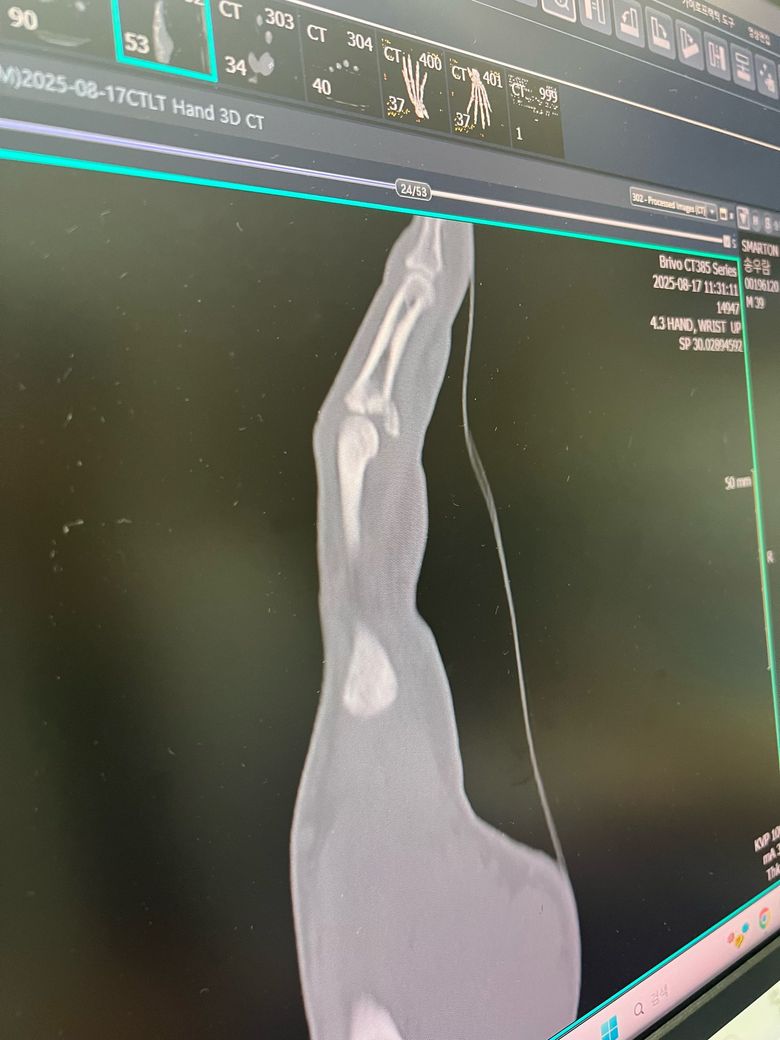

올려주신 엑스레이와 ct를 보면 손가락 뼈에 핀이 삽입되어 고정된 상태입니다. 핀은 뼈가 충분히 붙을 때까지 제거하지 않는 것이 안전하고 수술 후 5일 정도는 아직 뼈가 완전히 안정되지 않은 초기 상태입니다.